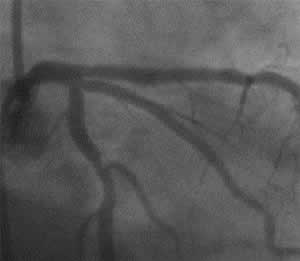

| Final CAG Findings: '01.8.28 LVG: no asynergy, EF: 61% CAG: #5 ostial 75%, #6 ostial 90% |

K-1 : 6 months follow-up angio